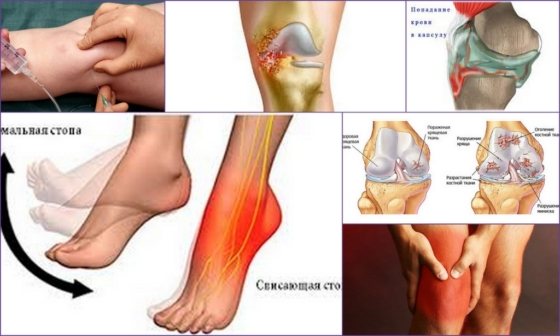

Артроцентез

Пункция проводится врачом с диагностической или лечебной целью, заключается в удалении из коленного сустава патологической жидкости: гноя, крови, экссудата с последующим введение лекарственных препаратов.

Выкачивание жидкости из колена не требует особой подготовки и проводится врачом ортопедом. Для осуществления манипуляции специалист выбирает безопасную точку: передневнутреннюю поверхность коленного сустава и проводит асептическую обработку операционного поля.

Перед удалением жидкости проводят местное обезболивание: тонкой иглой в окружающие ткани вводят анальгезирующее средство и через 1-2 минуты при помощи пальпации и устного опроса определяют степень обезболивания.

Пункционной иглой совершают прокол суставной капсулы, эвакуируют содержимое коленного сустава и по окончании процедуры проводят повторную обработку операционного поля с последующим наложением повязки.

Допустимо проведение артроцентеза под контролем УЗИ для предупреждения травматизации костей. Во время манипуляции используются ультразвуковые иглы с лазерными насечками.

Проведение процедуры откачивания жидкости из коленного сустава